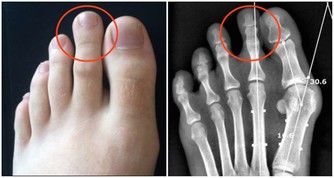

1、麻木

麻木和抽筋是血液循環不好的最初症狀。

可以在手足觀察到這類症狀,特別是腿部。

在過度活動後腿部變得過於疲勞和疼痛。

解決這一問題的方法之一是坐著或睡覺時抬高腿部,以減輕疼痛。

此外,血液循環不好還會造成身體某些部位紅腫。